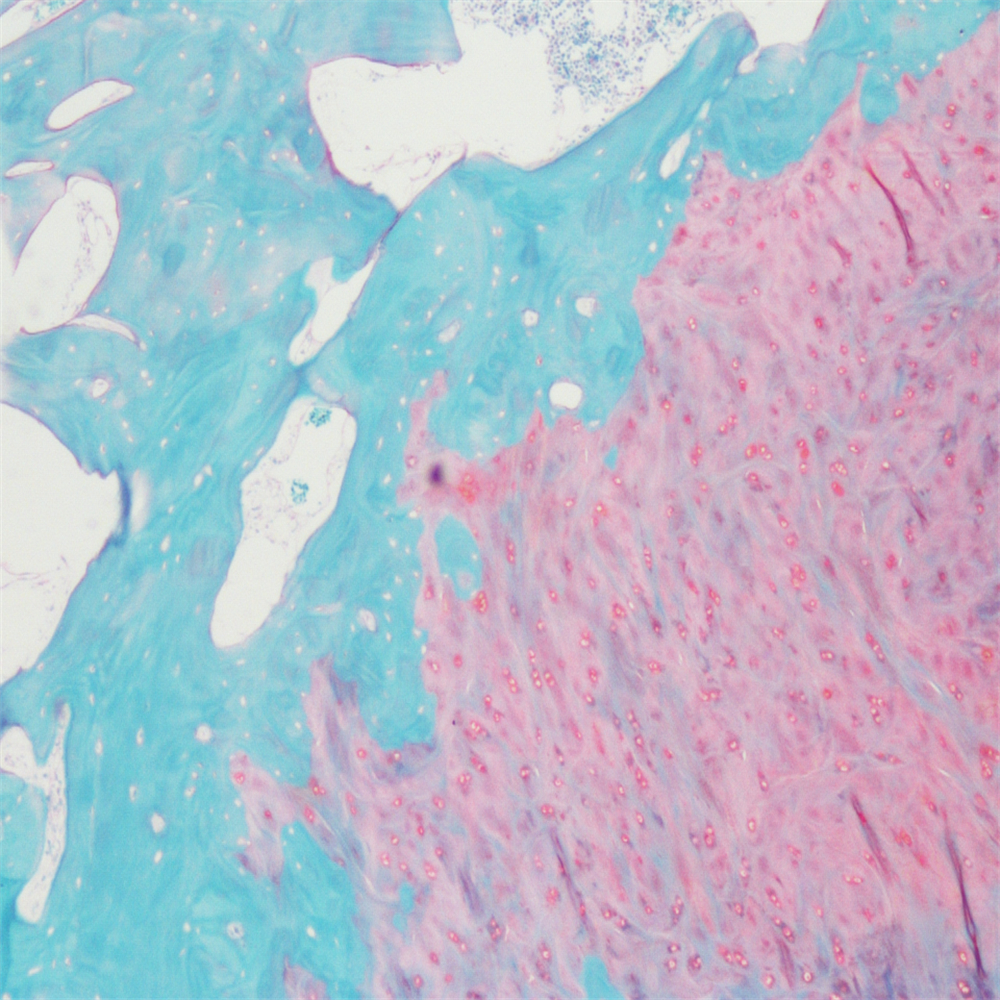

番红-固绿染色(软骨)在涉及关节软骨及软骨下骨的形态学研究中,常需联合使用多种染料以显示其组织学结构。其中,起源于上世纪60年代的番红O(safranin O)-固绿(fast green)染色因可以直观反映关节软骨、软骨下骨和骨组织的结构而备受青睐。软骨呈红色,成骨呈绿色。

番红-固绿(软骨)染色法的染色原理在于嗜碱性的软骨和碱性染料番红O结合呈现红色,嗜酸性的骨和酸性染料固绿结合而成绿色或者蓝色,与呈现红色的软骨对比鲜明,从而将软骨组织和骨组织区分开。番红O是一种结合多阴离子的阳离子染料,其显示软骨组织是基于阳离子染料与多糖中阴离子基团(硫酸软骨素或硫酸角质素)结合。番红O着色与阴离子的浓度近似成正比关系,间接反映基质中蛋白多糖的含量和分布。当软骨收到损伤时,软骨中的糖蛋白会释放出来,使基质成分分布不均匀,从而导致番红O淡染或不着色。通过图像分析软件可以对番红O染色的软骨基质进行定量分析。固绿与胶原纤维结合,不宜褪色。